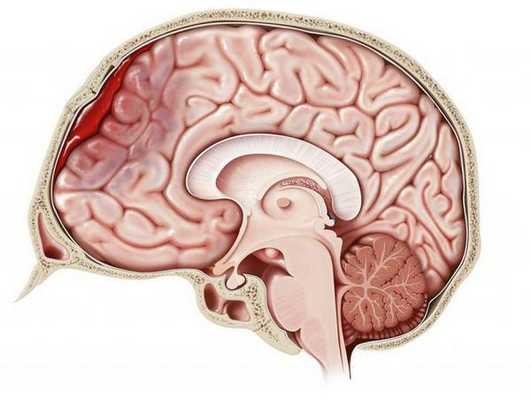

КТ головного мозга. Геморрагический инсульт, обширная интрапаренхиматозная гематома в левой гемисфере

Они позволяют определить объем и локализацию внутримозговой гематомы, степень дислокации мозга и сопутствующего отека, наличие и область распространения кровоизлияния. Желательно проведение повторных КТ-исследований, чтобы проследить эволюцию гематомы и состояние мозговой ткани в динамике.